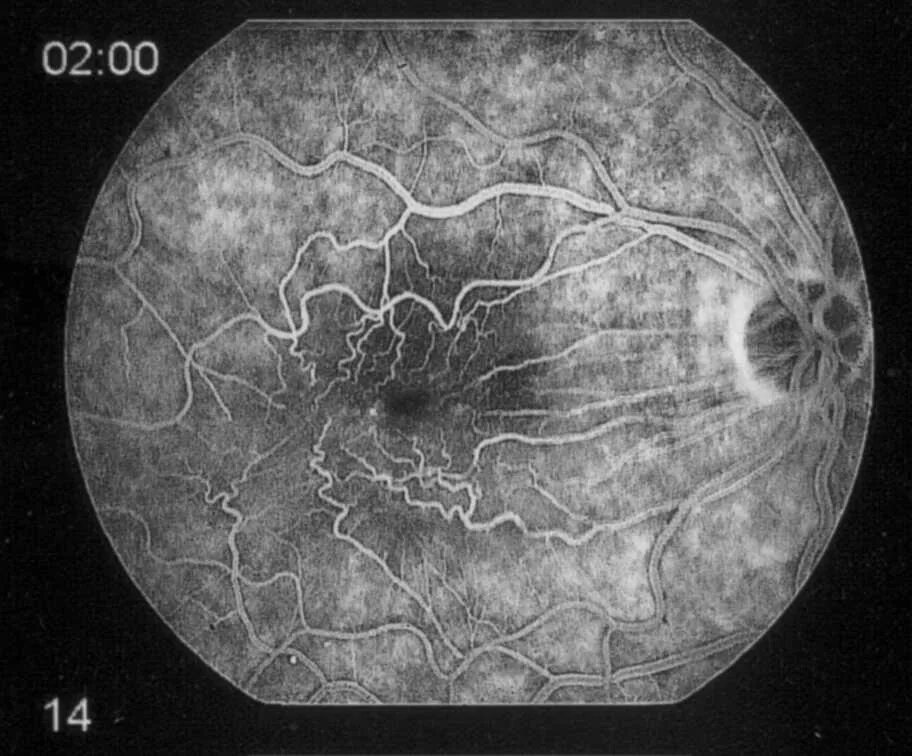

Эпиретинальный фиброз глаза что это